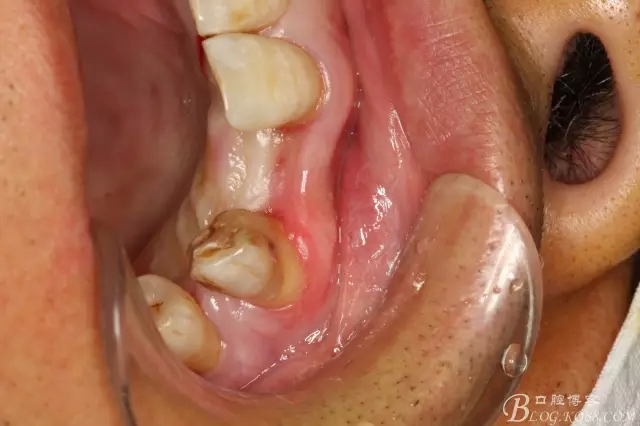

圖3.術(shù)前口內(nèi)照片:正面觀閉口位

圖4.左側(cè)側(cè)面觀,22間隙正常,23近中輕度扭轉(zhuǎn)

圖5.腭側(cè)觀:牙槽嵴豐滿度尚可。